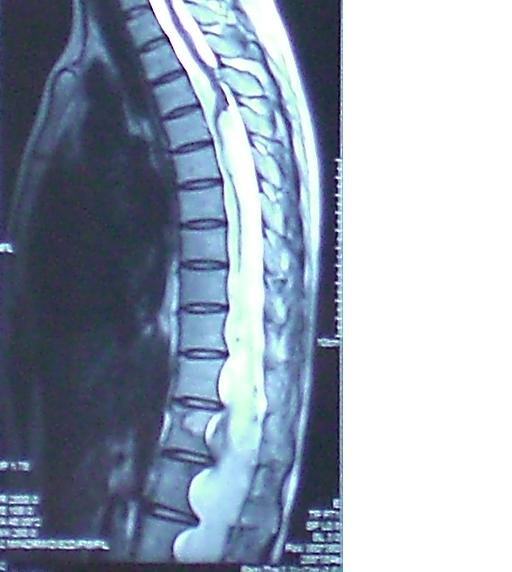

神经外科王振宇主任与马长城教授详细地询问病人的病史,为病人进行了细致的查体后怀疑患者存在脊髓的疾病,而为病人进行了脊髓的核磁检查,结果发现患者椎管内有巨大巨长的肿瘤,肿瘤上端至第五胸椎水平,一直延续到骶管的末端,占据整个椎管,而且由于对脊椎的长期压迫,已经使椎管明显扩大。